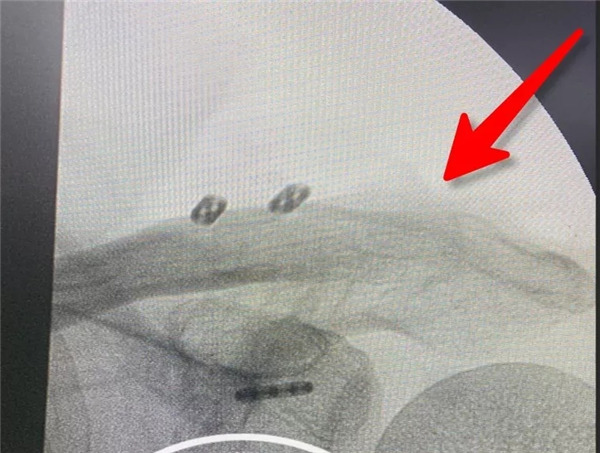

傳統(tǒng)手術(shù)方式——大切口上鋼板

據(jù)羅軍主任介紹,肩鎖關(guān)節(jié)脫位是一種較為常見(jiàn)的外傷性脫位,對(duì)于完全移位的Rockwood 4-6型脫位,以往的手術(shù)治療大多使用鎖骨鉤鋼板復(fù)位固定,包括鉤鋼板內(nèi)固定,喙鎖間螺釘固定術(shù),鎖骨外側(cè)端切除,肩鎖韌帶重建等術(shù)式,但是這些技術(shù)都存在著一定程度的缺陷,一是創(chuàng)傷較大,術(shù)后經(jīng)常出現(xiàn)肩部疼痛、活動(dòng)受限、肩峰骨質(zhì)溶解、肩峰下撞擊、應(yīng)力性骨折、脫鉤失效等并發(fā)癥,二是后期還需要二次手術(shù)取出鋼板。